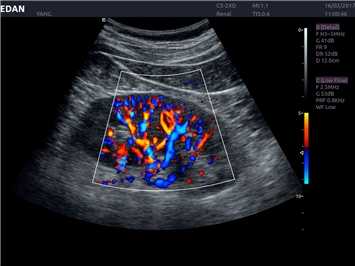

• Тканевая допплеровская визуализация (TDI)

• Сосудистой диагностики

Трехмерная реконструкция ЦДК:

Да

Энергетический допплер:

Цветовой допплер:

Color 3D: